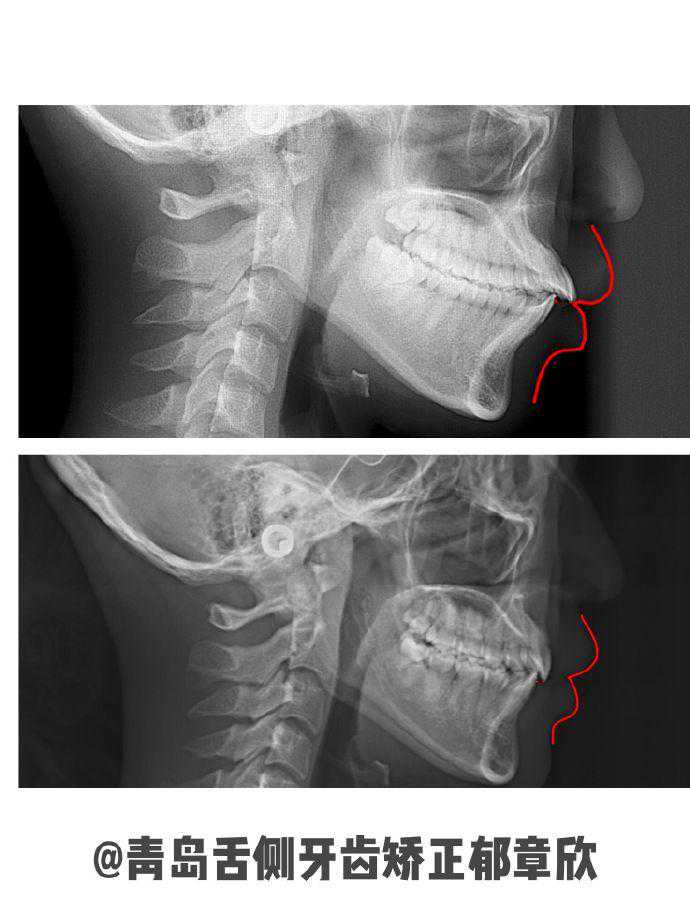

患者是骨性前突,面诊了几家外院给的建议是手术治疗。我通过CBCT和头影测量分析,观察到她的牙齿还有矫正空间,与她沟通了矫正后能达到的内收效果及面型的改善程度,她表示接受。

结合患者高效隐形的诉求,我为她选择了舌侧矫治器。方案设计拔除4颗正畸牙,使用MIA微种植钉支抗以辅助关闭拔牙间隙以及控制上前牙垂直方向移动,达到理想内收移动效果。一年半时间结束矫正,牙齿整齐内收,突面型改善,下巴挺现,侧貌轮廓更精致协调。